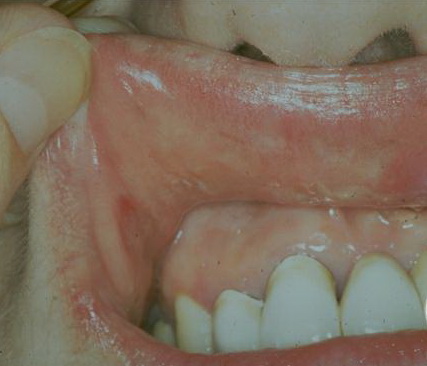

Secondary syphilis = الافرنجي الثانوي